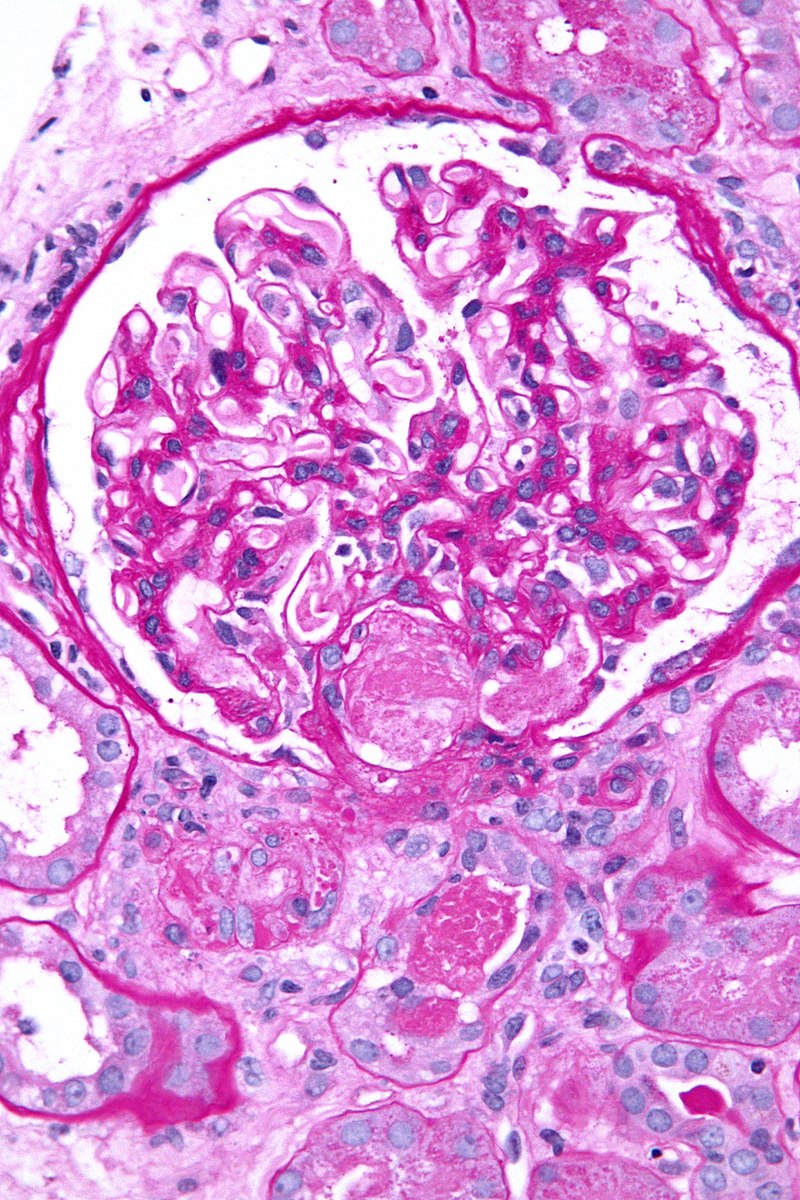

• Disseminated Intravascular Coagulation

Disseminated intravascular coagulation. Arrows indicate intravascular fibrin deposition. Clinical review: molecular mechanisms underlying the role of antithrombin in sepsis. Wiedermann CJ - Critical care (London, England) (2006). Not Altered. CC.